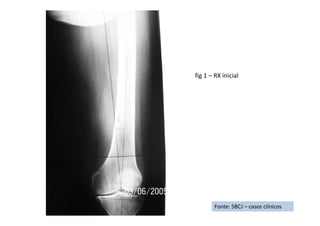

Fonte: SBCJ – casos clínicos

RX de Frente

RX de Perfil